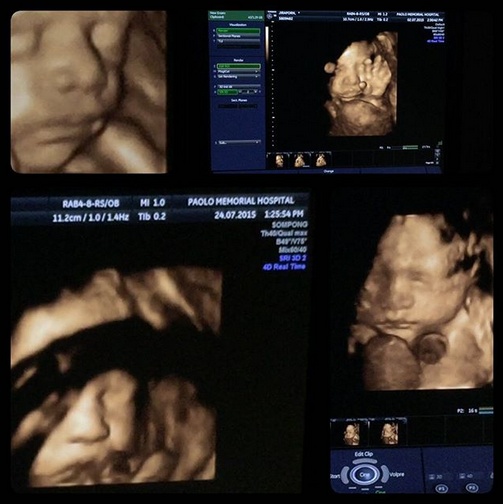

เปิดภาพ น้องแตงกวา ภรรยาคนสวยของ เอ พศิน ที่ตอนนี้กำลังอุ้มท้อง น้องเลโก้ เจ้าพระยา น่ารักจังเลย

เมื่อวันที่ 26 กรกฎาคม 2558 เอ พศิน ได้ออกมาเปิดเผยโฉมหน้าของน้องแตงกวา ภรรยาสาวแสนสวย ที่ตอนนี้กำลังอุ้มท้อง น้องเลโก้ เจ้าพระยา โดยที่ก่อนหน้านี้ เอได้ออกมายอมรับว่า ตนกำลังจะมีลูกจริง ๆ แต่เนื่องจากตนเป็นตัวร้าย เลยไม่ค่อยมีภาพทางพีอาร์เท่าไร ตนก็ใช้ชีวิตปกติ และได้จดทะเบียนสมรสกับภรรยาเรียบร้อยแล้ว ตนไม่เคยปิดเรื่องนี้ แต่ก็ไม่ต้องการเปิดตัวมากมาย

ภาพจาก Instagram lego_chaophaya